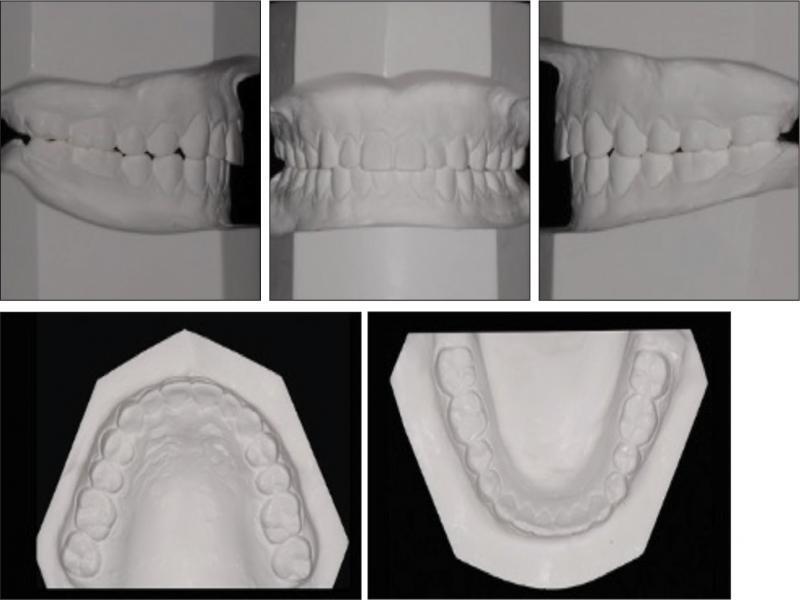

A 22-year-old female presented with the main complaint of “protrusive lips” and said she “would like to have treatment with clear aligners” because of her work as an actress. A facial analysis showed that there was a symmetrical face, a convex profile and a decreased nasolabial angle (Figure 1). No temporomandibular joint disorder was noted during the consultation and clinical examination. An intraoral assessment revealed that there was an Angle Class I molar relationship on her left side and a Class III relationship on the right side, a 1 mm overjet and overbite, and symmetrical dental arches with no crowding. Both upper and lower midlines were 1 mm to the left of the facial midline. No mandibular functional shift was observed (Figures 1 and 2).

Pretreatment facial and intraoral photographs.

Pretreatment dental casts.